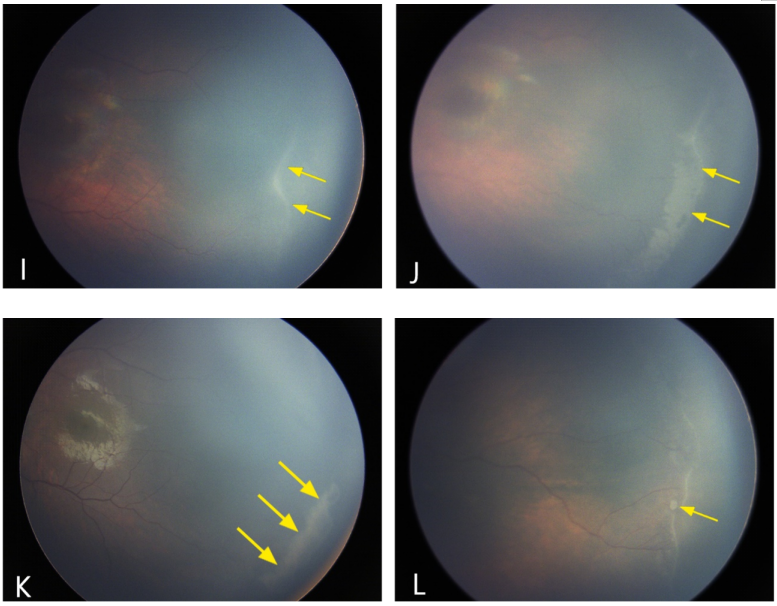

在ROP自然退行过程中还可观察到一些特殊的眼底表现。部分患儿的视网膜血管在ROP病变完成退行后依然没有完全恢复正常,甚至部分在病变急性期时视网膜血管未见迂曲扩张,但ROP病变退行后血管反而出现迂曲扩张(图4A、B)。14例(5.9%)患者在有-无血管交界处观察到动静脉分流或环形血管形成(图4C、D);尽管ROP退行,3例患儿动静脉分流或环形血管依然存在。此外可见21例(8.9%)ROP患儿伴RH,所有患儿RH均在病变退行完成前被吸收(图4E、F)。13例患儿视网膜嵴隆起不规则,在退行过程中这些不规则的嵴通常先逐渐变直,然后再逐渐消退(图4G、H)。然而,部分患儿的嵴在退行过程中并没有直接减小,相反会变为一个更大的平坦的条带样斑块,然后逐渐缓慢消退,这往往需要更长的时间(图4I ~ K)。在7名患儿中见“爆米花样”病变位于视网膜嵴的后方,并在嵴退行前消退(图4L)。

图4. ROP患儿自然退行过程中的特殊眼底表现